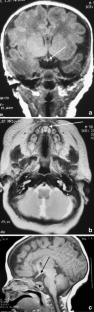

Patients with congenital hypopituitarism might have the classic triad of pituitary stalk interruption syndrome, which consists of: (1) an interrupted or thin pituitary stalk, (2) an absent or ectopic posterior pituitary (EPP), and (3) anterior pituitary hypoplasia or aplasia.

Fig. 2